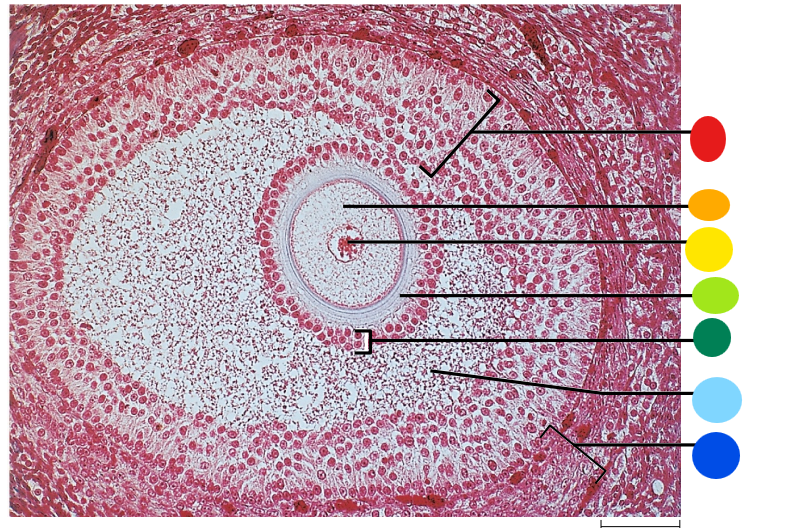

red

granulosa cells

orange

primary or secondary oocyte

yellow

oocyte nucleus

light green

zona pellucida

dark green

cumulus oophorus

light blue

antrum

dark blue

thecal cells

what is this

tertiary follicle